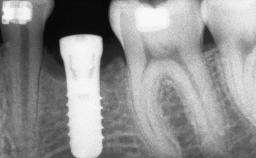

A 47-year-old woman who had suffered from aggressive periodontitis requiring a number of periodontal interventions over more than 10 years was referred by her general dental practitioner and periodontologist for bone augmentation and implant therapy. Her failing dentition had already been scheduled for extraction. The patient expressed a desire for implant-supported fixed restorations and esthetic improvement of her lower face. She had agreed to consult with a maxillofacial surgeon after the referring dentist had suggested bone augmentation. An initial examination by the maxillofacial surgeon revealed mobility of all residual teeth in a patient who was very unhappy with the function of her removable partial dentures. Due to periodontally migrated flaring teeth and loss of occlusal support, the vertical dimension of occlusion was dramatically reduced. The patient was displeased with her lower face because of deepened nasolabial, commissural, and supramental folds.

Type of Implants Two-Piece

Bone Augmentation Horizontal|Sinus Floor Elevation|Staged|Vertical